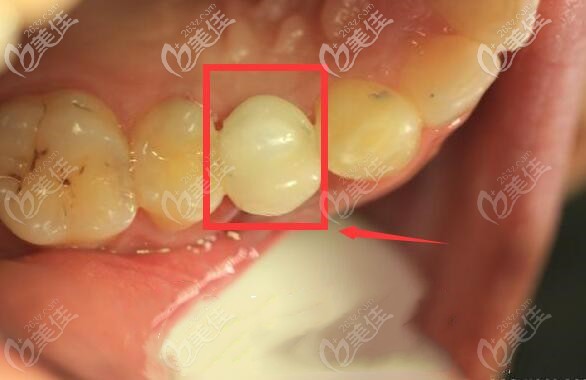

后经过六个月的观察后发现修复效果良好,从图片可以看出哪个是种植牙吗?

种植牙修复后,种植体与牙槽骨紧密结合,种植牙与真牙外观极其相似,上下牙咬合正常,种植体周边无骨吸收情况。可以说手术是很成功的。